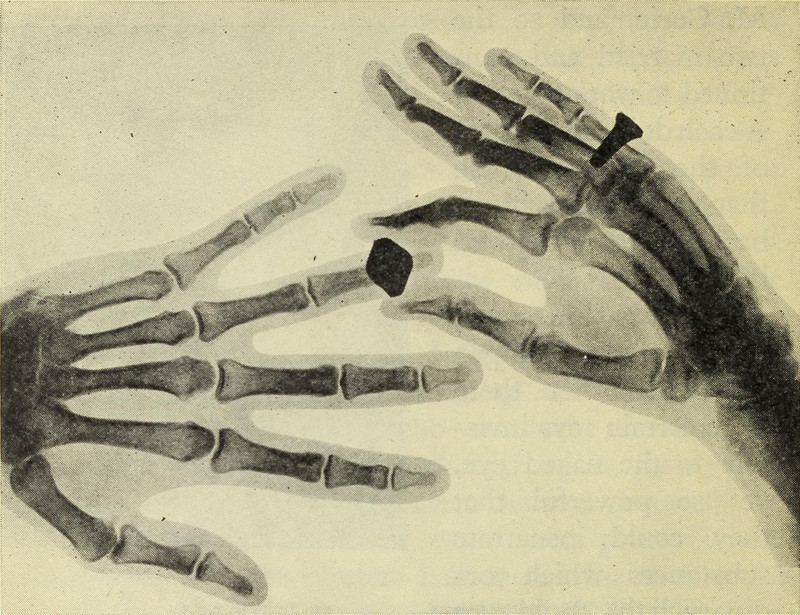

Images Moving Through Time (permalink)

From Britain's Story III by Hannah Bellis, 1935.

#vintage illustration #ring #x-ray #hand #1930s #jewelry #illustration #xray